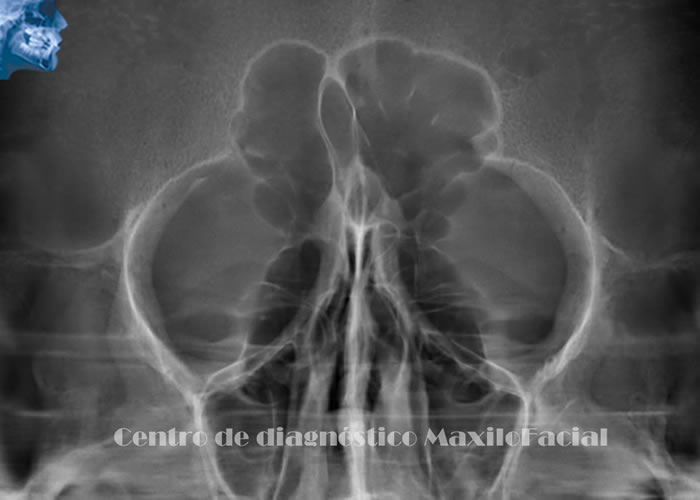

Otras Técnicas Radiográficas Dentales

Ofrecen una visión complementaria para evaluar senos maxilares, fracturas de cóndilos, asimetrías faciales, etc. Dependiendo de la zona de interés.